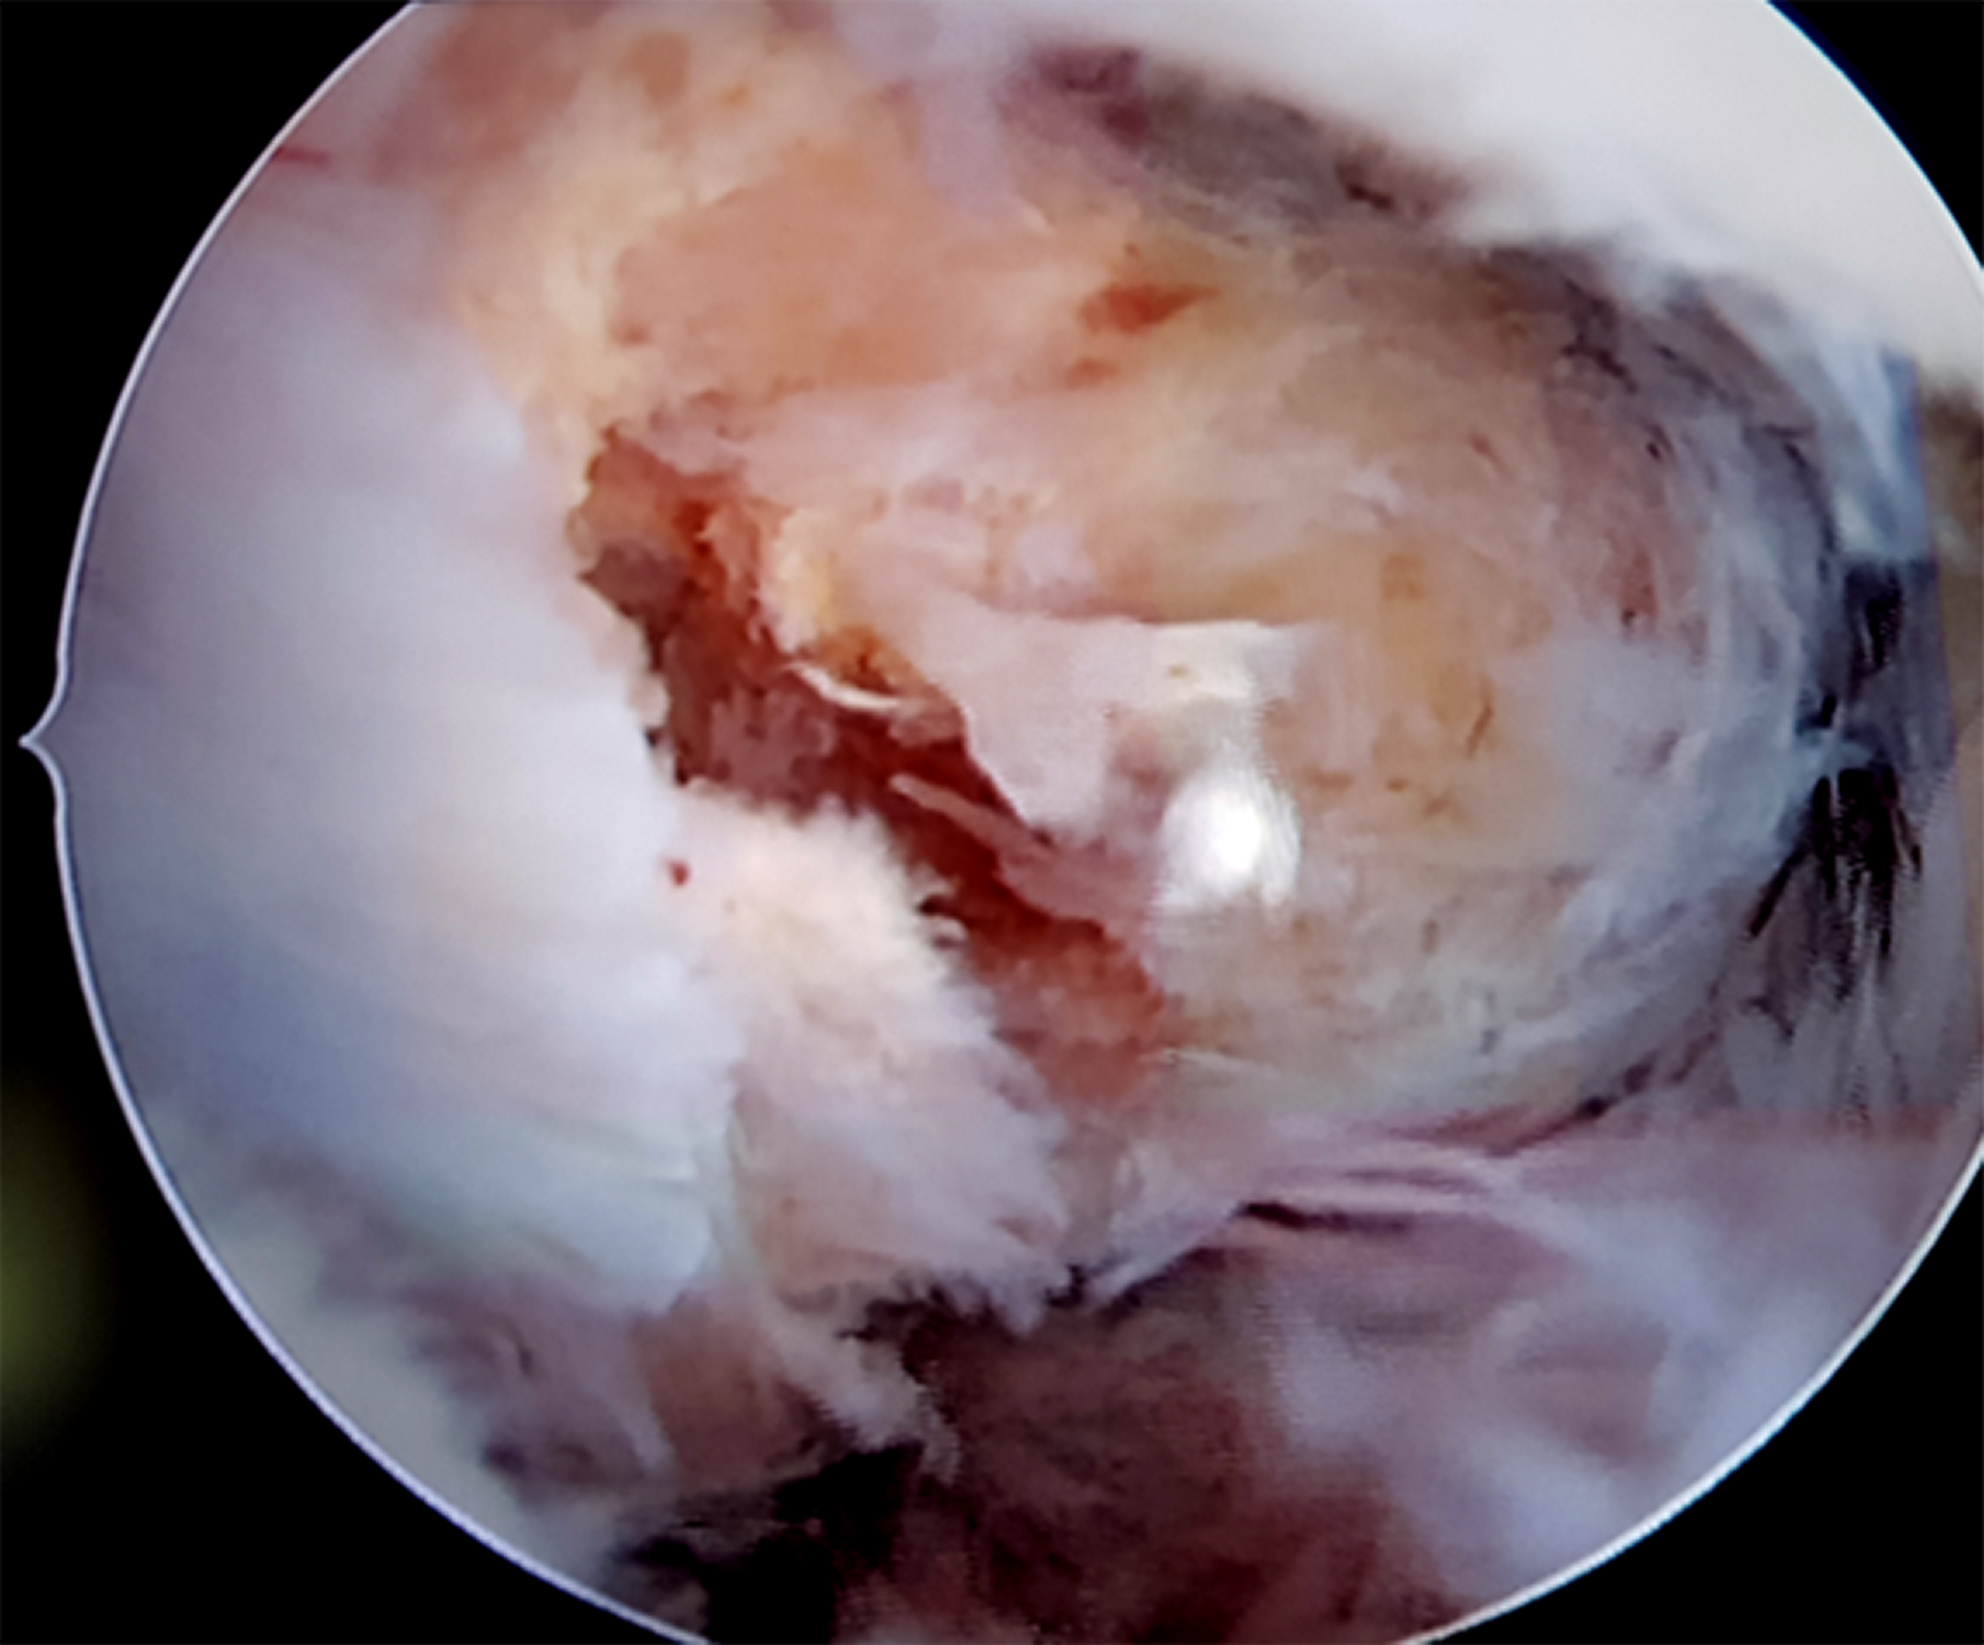

El paciente fue derivado al equipo de artroscopia de rodilla para evaluar la resección artroscópica de la misma. Se realizaron tres portales. El portal AL y AM estándar con objetivo el desbridamiento periférico en región anterior con preservación marginal. El portal PM con el objeto del desbridamiento periférico posterior y la exéresis en bloque de la pieza, lo cual se logro sin dificultad ni necesidad de realizar artrotomía (figs. 3, 4 y 5).

Figuras 3, 4 y 5: Superior derecha e izquierda: Se observa visión artroscópica por portal anterolateral y posteromedial, localización retro LCP. Inferior: Visualización artroscópica posterior a exéresis completa.